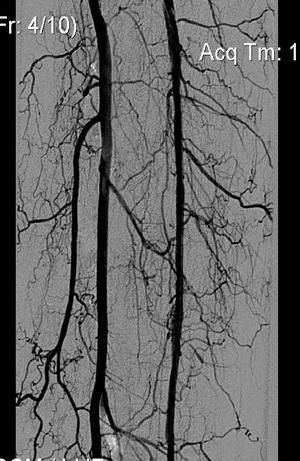

Контроль через месяц - ПББА проходима с участком короткой окклюзии, проведено повторно ЧБА коротким коронарным баллоном и стентирование стентом Cypher.